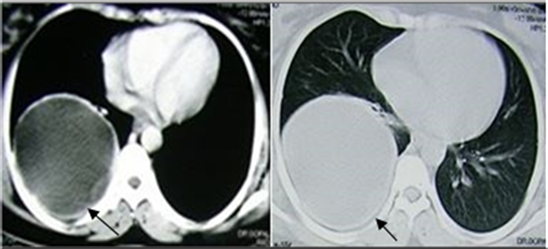

Figure 3. Class CE1 Hydatid cyst in pancreas in a 16 yr old female patient with history of abdominal discomfort. Plain and CECT abdomen showed rounded, unilocular cystic lesion with thin high attenuation rim with no enhancement on postcontrast involving body and tail of pancreas.

Figure 4. Class CE2 hydatid cyst in right lung in a 35 yr female patient with history of cough, expectoration and fever. Plain and CECT chest revealed rounded, thin walled, unilocular cystic lesion with daughter cyst within, with no enhancement on postcontrast.

CT is the modality of choice in case of HC located in lung, bone, cysts with wall calcifications in other location to demonstrate the internal morphology [Figure 4 and Figures 6-12]. And plays vital role in preoperative evaluation for detection of complications such as biliary, vascular and bronchial involvement, cyst ruptures, and underlying infections [Figure 6, Figure 9, Figures 11-14]. Unruptured cyst is differentiated from other simple cysts by the presence of high

Figure 6. Class CE3 hydatid cyst in upper lobe right lung with associated atelectasis and mild cylindrical bronchiectasis and Class CE2 hydatid cyst in liver in a 25 yr female patient with h/o fever, cough with expectoration. Plain and CECT chest showed well defined, thin walled cystic lesion with “floating membranes within” with no enhancement on postcontrast and adjacent atelectasis with mild cylindrical bronchiectasis. Liver showed thin walled, multivesicular cystic lesion with attenuation of mother cyst is higher than that of daughter cysts with no enhancement on postcontrast.